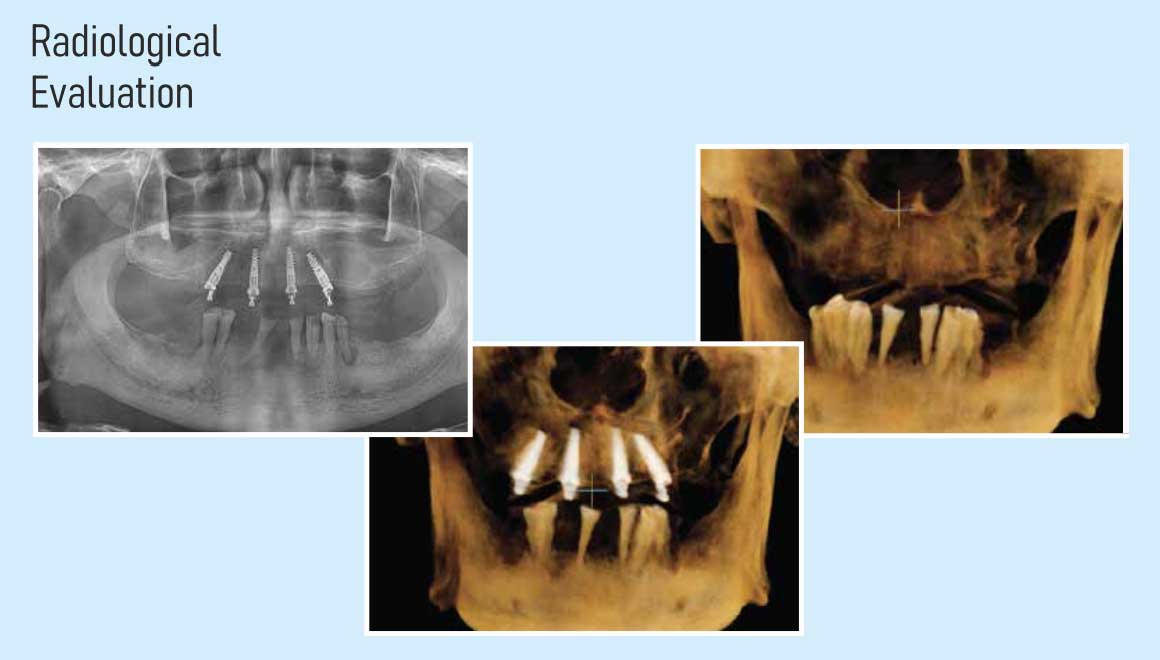

In House Radio Visual Graphics (RVG)

We are using low dose chair side portable radiology with radio visual graphic system which is absolutely vital for accurate planning and placement of impant.it also helps in the accurate evaluation of critical structure, like nerves teeth roots, sinus etc., thereby eliminating any chances of failure occurring due to misdiagnosis.

Our implant centers are equipped with these state-of-the-art machines to ensure a flawless execution of absolutely any type of implant case.